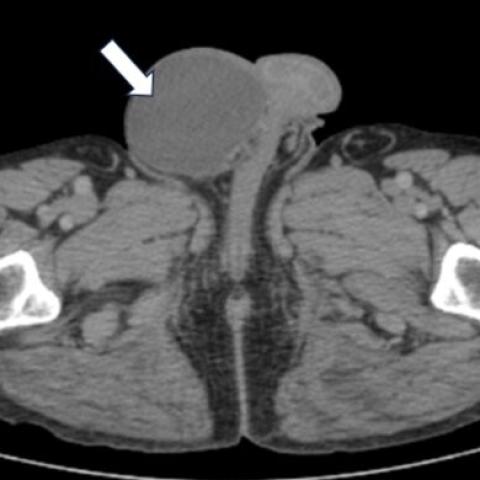

CT扫描示多个非典型位置的转移灶。这些转移灶在影像学上呈现出相似的特征,表现为低密度改变。转移灶的分布广泛,涉及心脏内部(右心室和左心室)、纵隔(后纵隔)、腹腔、左侧前腹壁以及右侧阴囊。

右侧阴囊低密度肿块(白色箭头)。